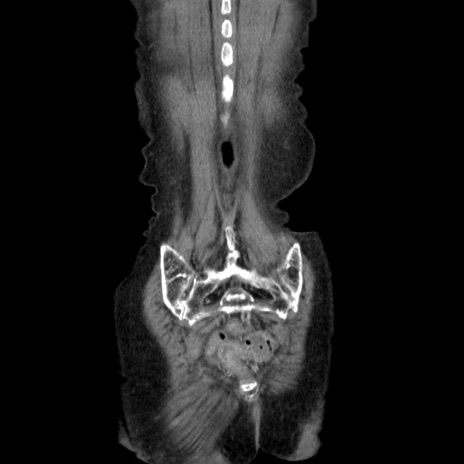

症例25(冠状断像)

【症例】80歳代女性

【主訴】胸のつかえ感

【現病歴】約9時間前に食後から胸のつかえた感じあり、嘔吐あり、来院。

【既往歴】胃癌(全摘)、胆摘、虫垂炎

【身体所見】心窩部に圧痛あり、反跳痛なし。

【データ】WBC 5700、CRP 0.05